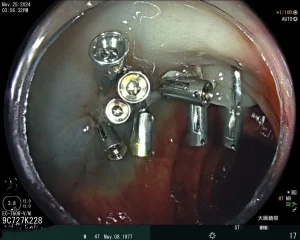

我們迎來豐田之山診所在手術房的第一台‘’黏膜下腫瘤切除術‘’。

以往只能在醫院做的處置,是因為一般診所的設備不足。

當我們設備超越醫院,缺的只是開始的契機。

在麻醉醫師的配合下,術式進行順利。世間又少了一個大腸癌的候選人。